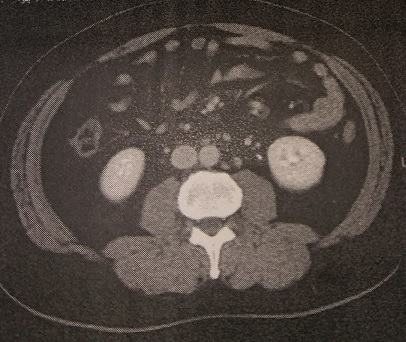

11/21にCTをとり、本日採血と結果を聞いてきました。

→11/21 CT検査

CT結果。

CT結果は良好。血は相変わらず。

CB先生「CTは問題ありません。3年経ったらCTは1年おきでいいですね。次回は2017/5月CTで。」